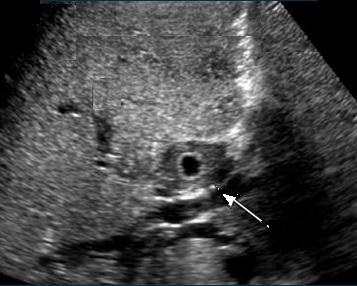

Echographie percutane

: Images echographiques du cholangite

infectueuse

aigue : Dilatation des voie biliaire intra et

extrahepatique , depasse 8mm avec voie

extrahepatique et 4mm des voies intrahepatique ,

Epaissisement de hypoattenuant de sa paroi . Image

de calcul canalicules et parfois de la

presence de pus intracanalaire .

Image

dilatation de voie biliaire intrahepatique.

Sa diametre de passe 6mm et image de calcul

vesiculaire se envoayait tres nette sur ce

coupe . Cholangite infectueuse |

echographique d'une cholangite

infectueuse aigue d'une voie biliaire en

coupe a transverse du canal . Le canal est

dilate avec image de epaissisemenmt tres

marque de la paroi( fleche b;lanche ) . Les

autres voies biliaires intrahepatiques

dilatees peut en voyaient sur meme coupe . |